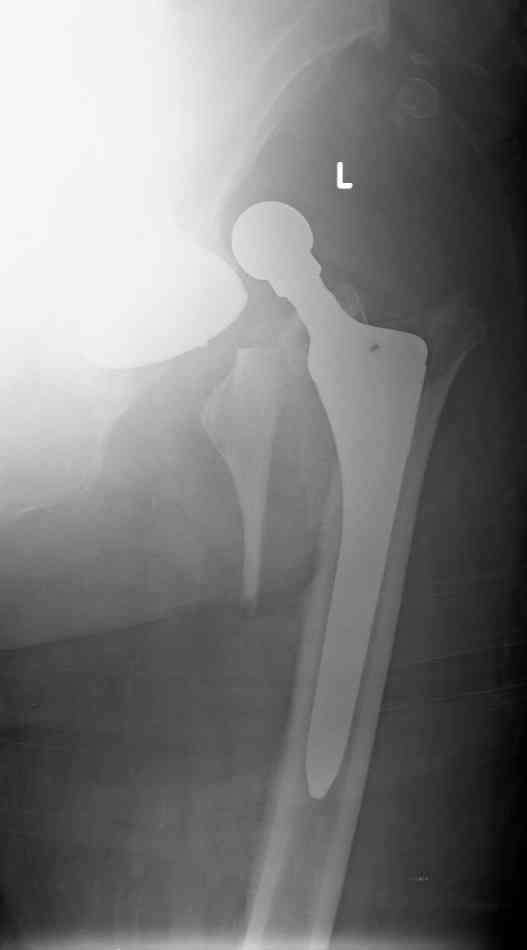

Patient 77 yaers old man falled two day after elective THR operation.

Was done noncemented THR,Direct Lateral Approuch .During posedure wasn't any complication.Now we have Vancouver AL fracture (to be more prosize between A to B1).What your sudgests?

2. Fracture - In terms of classification doesn't fit neatly into Vancouver Classification because both lesser & greater trochanters are fractured - therefore is AL & AG.

Medial fracture line extends into diaphysis and would therefore be more accurately defined as a B fracture. The stem looks like a Zimmer proximally coated FMT therefore as it is only 2 days post-op & given the morphology of the fracture probably best described as a B2 fracture around loose stem.

Treatment - Revision surgery to include -

1. Stem revision to stem which allowed distal fixation - ie fully coated porous or tapered distal fixation stem.

2. Reduction of medial calcar fragment & greater

trochanter probably best achieved with rochanteric cable plate system

3. Regarding instability - offset was obviously an issue in primary surgery given long neck skirted head. Therefore I would advise careful intra-operative assessment of socket position and abductor damage. If component position poor then revisie socket if not increase head size to 36mm

(which will also lateralise liner helping offset) or if abductor damage significant consider constrained liner (the Trilogy socket that is in place will allow for both these options).

Good evening!In the morning operation was done.

Socket is acceptable position so wasn't change.Fracture proximal femur - three part I mean G.T & L.T. After removal femoral prosthesis was done reduction of L.T & Calca. Reaming and insert new prosthesis with distal locking by 3 screws,reduction G.T.and fixation by 4 cyrclages.

Connection head and reduction femur.In the end surgery got stable joint.

Here x-ray after operation.